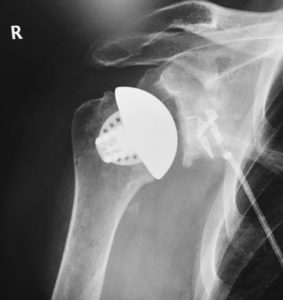

Equinoxe® Schaftloses Schultersystem

- Das innovative Cage-Glenoid verfügt über einen zentralen press-fit Hohlzapfen und drei periphere zementierte Zapfen.

- Verschiedene Humeruskopfe mit unterschiedlicher Höhe in abgestuften Größen – für eine optimale Weichteilspannung und Wiederherstellung der Biomechanik.

Das knochenerhaltende Prothesendesign ermöglicht einen späteren Umbau auf ein schaftbasiertes System.